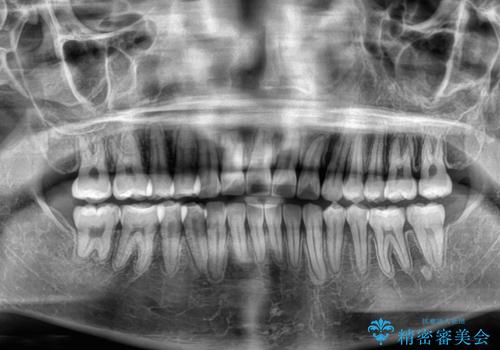

上顎の拡大は、左右どちらに拡大していくのか予想が困難ですが、こちらの患者様では結果として上下正中が一致する方向に拡大され、非常にきれいな仕上がりとなりました。